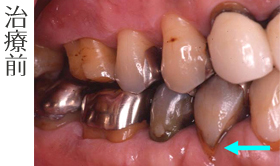

【審美歯科の治療事例】

歯根の露出の再生

歯茎が下がって根っこが見えてきています。